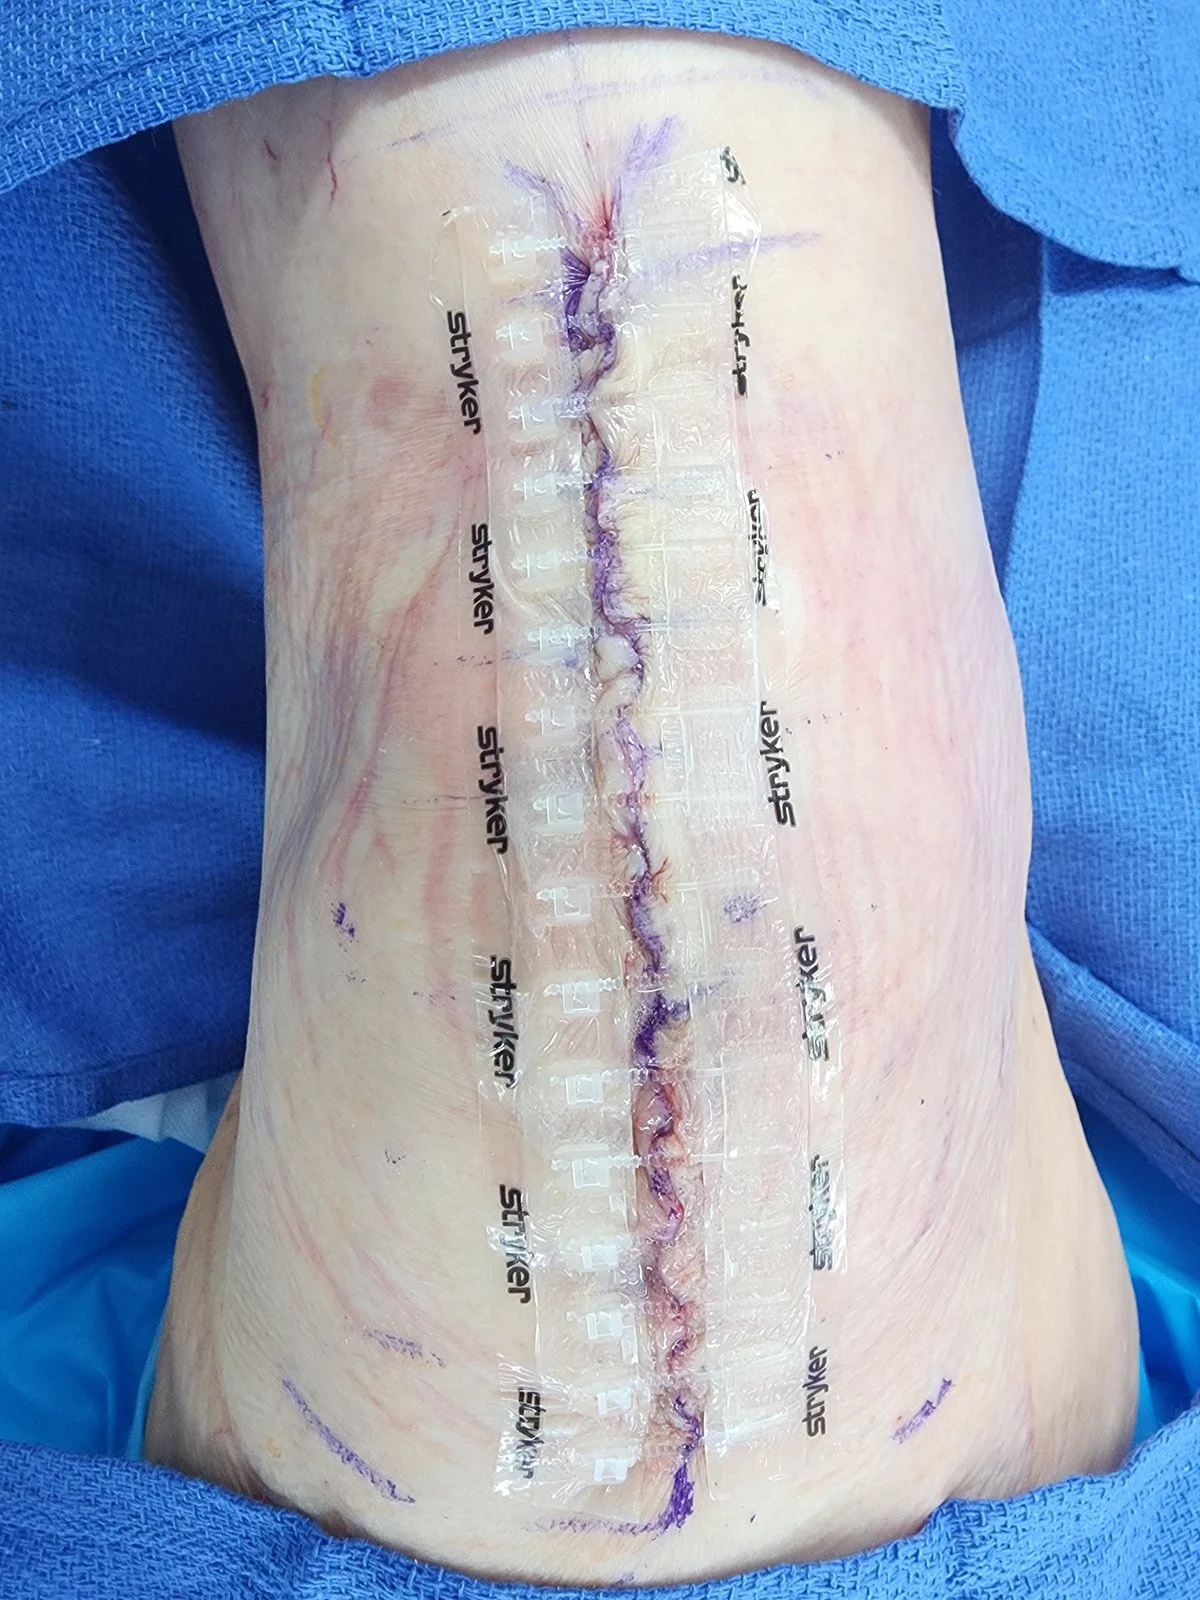

Dressings

Your wound will be covered with a waterproof dressing.

It is ok to shower after surgery. It is important to keep your dressing on, do not remove the dressing. It will be removed for you at your first postoperative visit.

If your dressing becomes saturated with blood or fluid, call the office to let us know so we may assess the wound. Underneath the dressing you have a removable dressing that is designed to stay on for 4 weeks.

You may peel this dressing off 4 weeks after surgery. If it begins to peel off on its own, you may remove it early.

If you have received collagen, you will remove the outer dressings, leaving the zipline dressing underneath in place 1 week after surgery. You will then apply the collagen dressing daily after showering for 4 weeks.